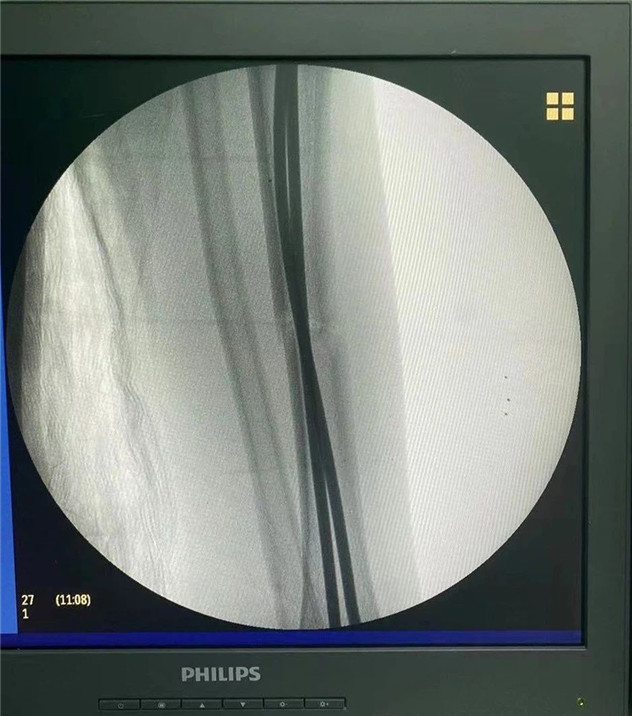

術(shù)中

2020年10月5日,在完成術(shù)前檢查后,睿睿接受了閉合復(fù)位彈性釘內(nèi)固定術(shù),手術(shù)由羅軍主任主刀。術(shù)中只需要兩個(gè)1厘米的小切口,精準(zhǔn)微創(chuàng),僅一個(gè)小時(shí),手術(shù)便圓滿完成。